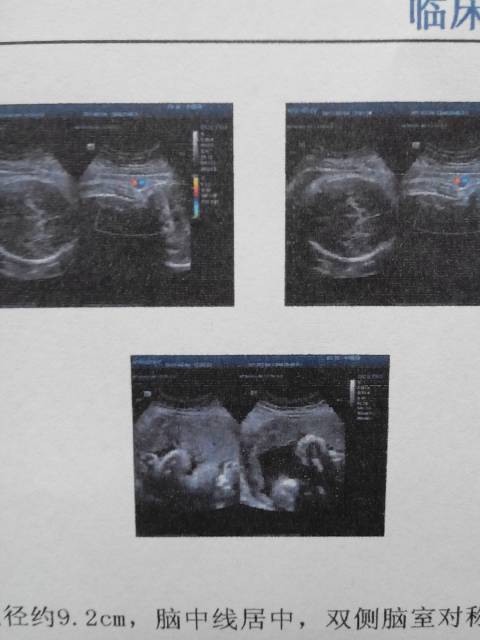

怀孕40周,刚做彩超,胎儿双顶径约9.2cm,脑中线居中,双侧脑室对称!等大!胎儿脊柱排列整齐,胸腹壁连线完整。可见胎动!胎心率约135/一次!请问谁能看出来,是男孩还是女孩啊

你好,这是正常成熟胎儿的超声报吴峡告,数据都是正常的,宝宝发育很好。这个上面看电筝坐不出来性别,国内目前是禁止胎儿性别鉴定的,所以检查单上也不会有这方面信息体现评悼。反正都快要生了,建议不必刻意追求,是男是女顺其自然,只要宝宝健康就好。